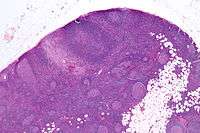

| Micrograph of a lymph node biopsy showing progressive transformation of germinal centres. H&E stain. | |

Microscopic appearance

PTGCs is characterized by:[1]

- follicular hyperplasia (many follicles),

- focally large germinal centres, with poorly demarcated germinal centre (GC)/mantle zone interfaces (as GCs infiltrated by mantle zone lymphocytes), and

- an expanded mantle zone.